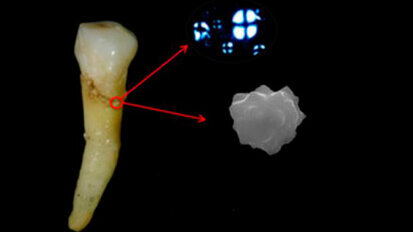

Ricerca: scoperto un legame fra problemi di capelli e carie dentali

Un comunicato dell’ADN Kronos riferisce che in occasione del 93esimo Meeting dell'International Association for Dental Research svoltosi a Boston ...